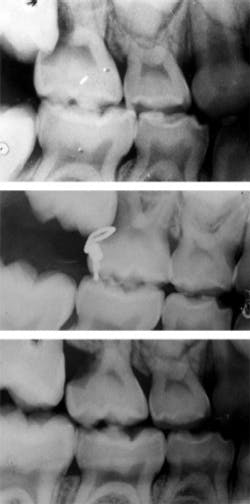

Other findings also often require orthodontic intervention. Posterior crossbites, whether unilateral or bilateral, require orthodontic treatment to correct. Early exfoliation of deciduous teeth (such as lower primary canine exfoliation upon eruption of permanent lateral incisor), or delayed eruption of permanent teeth may also warrant orthodontic involvement to allow for a proper and stable eruption of permanent teeth. Mobility of the permanent dentition, which may present itself in incisors as ectopic canines resorb their roots (see Figure 2), can also be a cause for concern and requires additional evaluation.